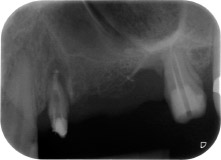

apical periodontal lesion at tooth 24

Fig. 1: 58-year-old patient. Preoperative radiograph showing an apical periodontal lesion at tooth 24 and horizontal loss of alveolar bone in the second quadrant.

A 58-year-old female patient complained of pain and increased mobility of her bridge abutment tooth 24. Periodontal inflammation was present with pocket depths of 7 mm mesiobuccally and more than 12 mm distally, as well as third-degree furcation involvement. Moreover, the radiograph revealed an extensive periodontal lesion around the apical region of the (alio loco) endodontically pretreated tooth 24 (Fig. 1).

One year earlier, teeth 25 and 26 had been extracted due to trauma and for endo-perio reasons, prior to the placement of the bridge. A combined endo-perio lesion was diagnosed for tooth 24, of unclear aetiology. The patient wanted to keep her bridge abutment teeth 24 and 27 and would not accept a final, or even temporary, removable prosthesis. Therefore, it was agreed to make all efforts to retain both teeth, in spite of their poor prognosis as based on radiological and clinical findings.

Placement of two submerged implants was planned at sites 25 and 26, in a surgical session with open periodontal debridement and apicoectomy of tooth 24. Due to the vertical bone deficiency at the future implant site, an internal sinus augmentation was also planned.